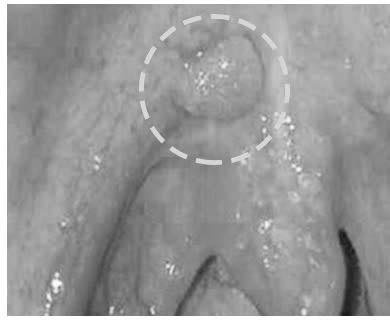

• Xuất hiện u nhú màu trắng ở lợi hoặc niêm mạc má, thường không gây đau nên dễ bị bỏ qua.

• Các chấm trắng trên nền niêm mạc bình thường, bề mặt gồ ghề, bờ viền không đều.